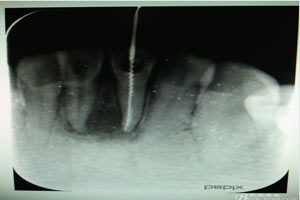

圖5.31、41試主尖,發(fā)現(xiàn)31根尖1/3有外吸收,糊劑有外溢現(xiàn)象。

圖6.根管治療+樹(shù)脂充填后根尖片影像:31根尖1/3大量根充物溢出。因此必須同期根管外科治療